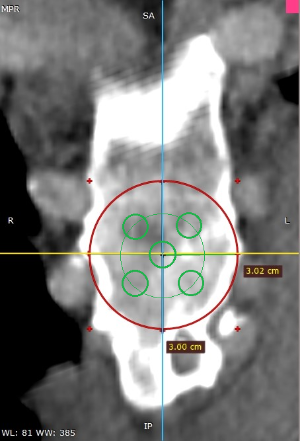

Los datos médicos del paciente, más la exploración clínica realizada por el equipo de cirugía, junto a un análisis pormenorizado de las imágenes del TAC y las reconstrucciones digitales en 3D de cada tórax realizadas conjuntamente con el equipo de ingenieros de Ventura Medical Technologies, son la base para determinar si la técnica Pectus Up está indicada y como se debe proceder en cada uno de los pacientes.

Con estos datos se selecciona el implante que mejor se ajustar a la anatomía de cada tórax, la ubicación exacta del sistema de elevación y, a su vez, proporciona al equipo quirúrgico un detalle de los pasos a tener en cuenta para llevar a cabo una correcta implantación.

| Pectus Excavatum | Pectus Excavatum Asimétrico |

|---|---|

| Índice de Asimetría | 0.6 (+R/-L)(|AI|> 0.05 Asimétrico) |

| Índice de Haller | 4.5 (HI >3.5) |

| Índice de Corrección | 49.13% |

| Rotación esternal | 18.1 ° (a la derecha) |

Informe de evaluación del TAC de un paciente enviada al cirujano